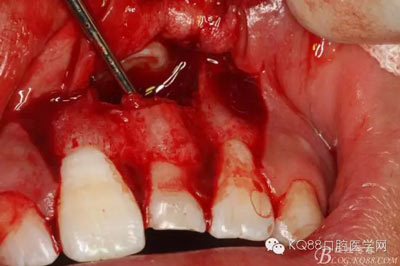

圖16.牙冠上方覆蓋膠原蛋白膜

圖17.骨壁重新覆蓋回去

圖18.縫合